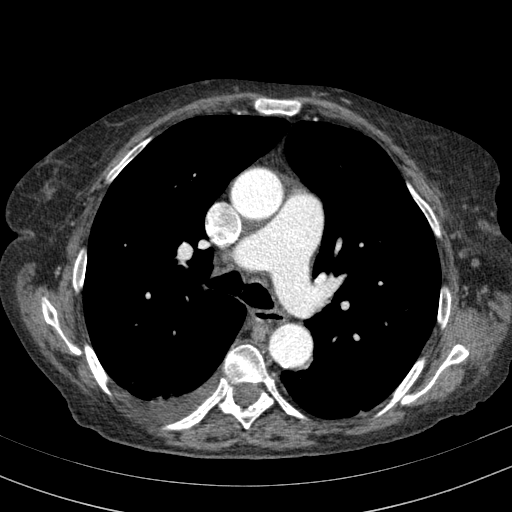

Original VENOUS CT scan

Full window (WL 1023.5, WW 4095 β†’ Low βˆ’1024, High +3071)

Actual HU range: [-160.0, 240.0]